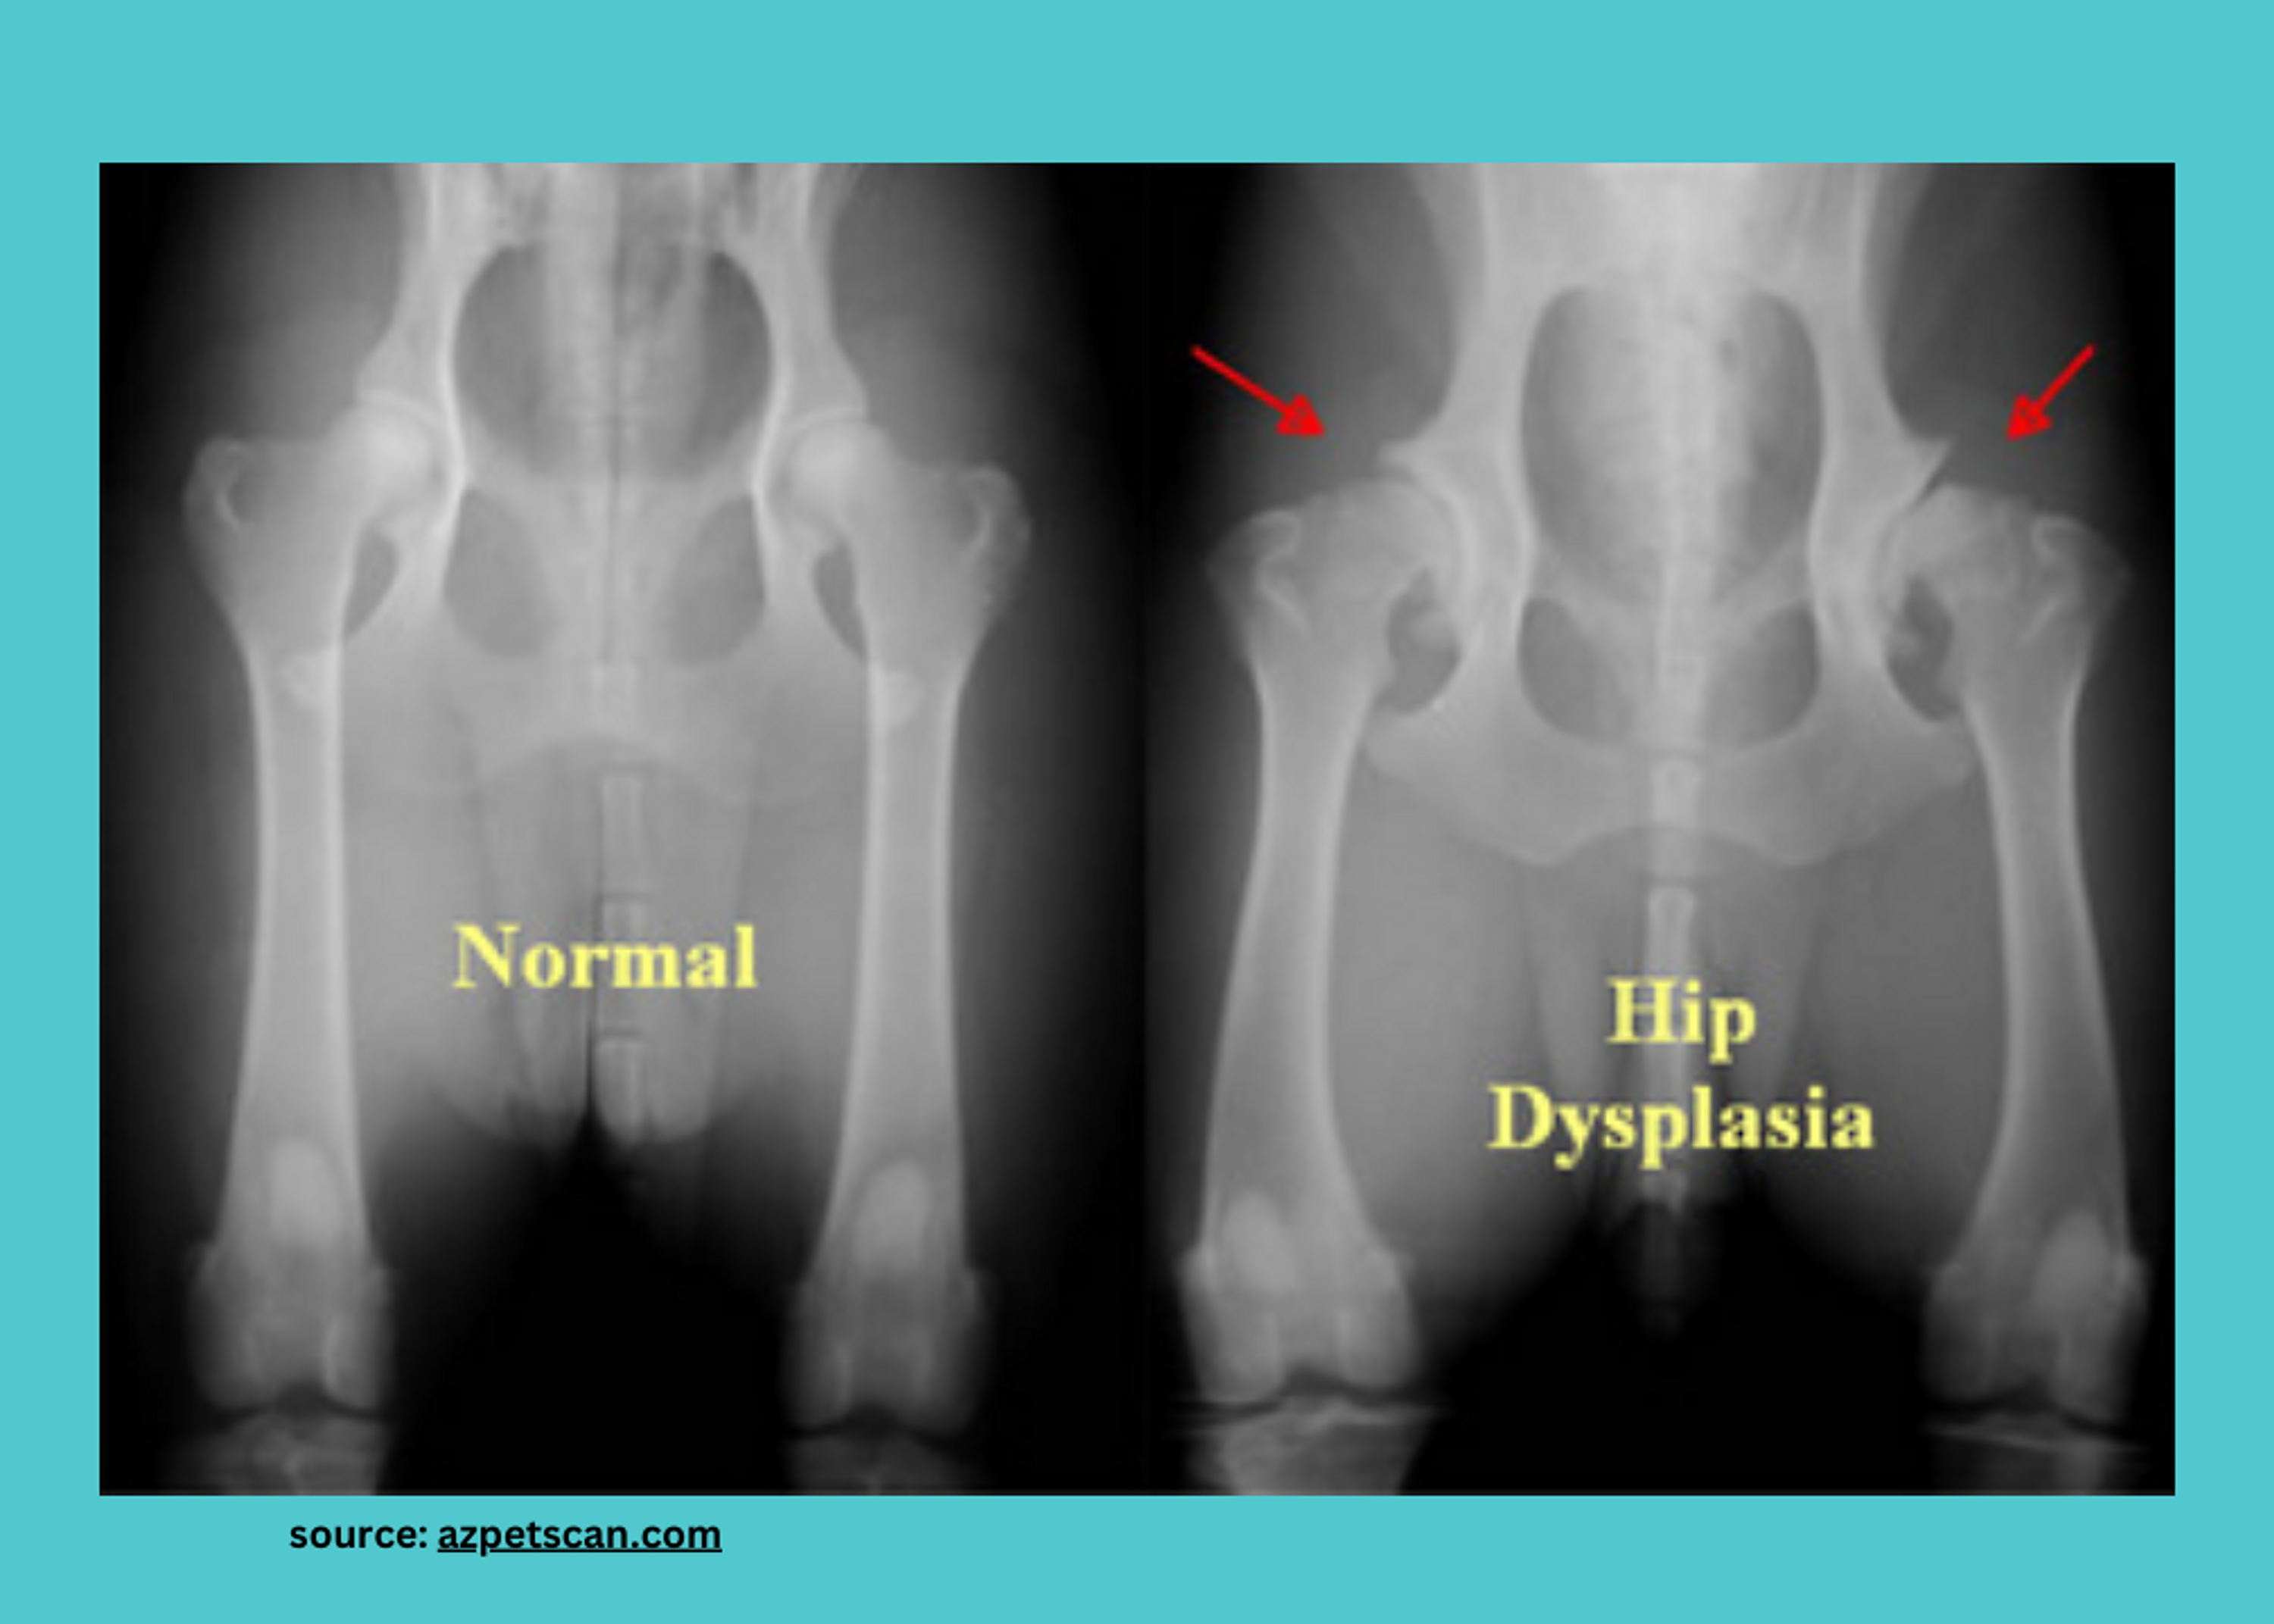

What is Hip Dysplasia?

Hip dysplasia is typically a common skeletal condition where the hip joint doesn't develop properly. Instead of fitting snugly into the hip socket, the ball-and-socket joint of the hip becomes loose and unstable. Over time, this leads to excessive wear and tear on the joint, causing pain and discomfort.